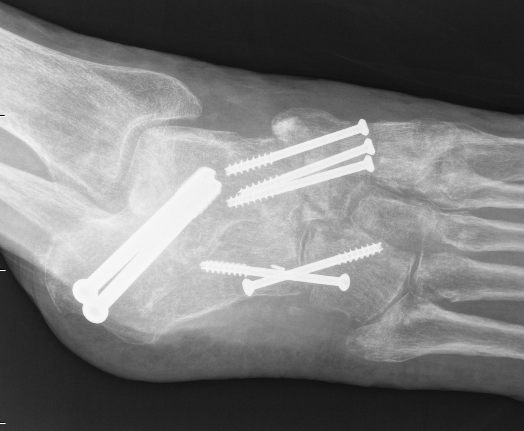

Evans Calcaneal Lengthening Osteotomy

Technique

Incision over anterolateral distal calcaneum

- sural nerve retracted plantar

- P longus retracted plantar

- identify CCJ

- Z lengthen P brevis

- homan retractor in sinus tarsi (between middle and anterior facets)

- homan retractor inferior calcaneum

- K wire into CCJ to prevent subluxation

Opening wedge osteotomy

- 1.5cm proximal to CCJ

- between middle and anterior facets medially

- begin with saw, complete with osteotome

- open 1 cm

- triangular / trapezoidal bone graft (allograft, iliac crest / mid fibular autograft)

- fixation with plate / staple / screw

+/- tendoachilles lengthening

+/- modified Kidner procedure (imbricate spring ligament, Tibialis posterior advancement)